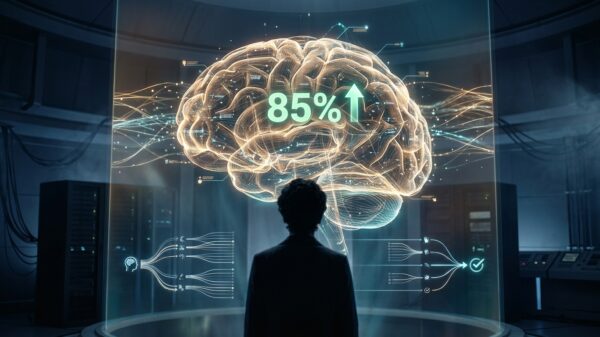

Generative AI achieves over 85% accuracy in predicting mental health treatment success, marking a pivotal shift toward Precision Psychiatry with $10 billion market potential...